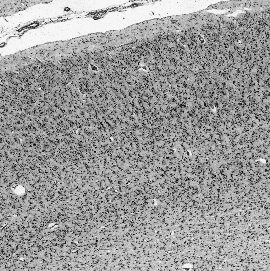

Cytoarchitectonic maps provide microstructural reference parcellations of the brain, describing its organization in terms of the spatial arrangement of neuronal cell bodies as measured from histological tissue sections. Recent work provided the first automatic segmentations of cytoarchitectonic areas in the visual system using Convolutional Neural Networks. We aim to extend this approach to become applicable to a wider range of brain areas, envisioning a solution for mapping the complete human brain. Inspired by recent success in image classification, we propose a contrastive learning objective for encoding microscopic image patches into robust microstructural features, which are efficient for cytoarchitectonic area classification. We show that a model pre-trained using this learning task outperforms a model trained from scratch, as well as a model pre-trained on a recently proposed auxiliary task. We perform cluster analysis in the feature space to show that the learned representations form anatomically meaningful groups.